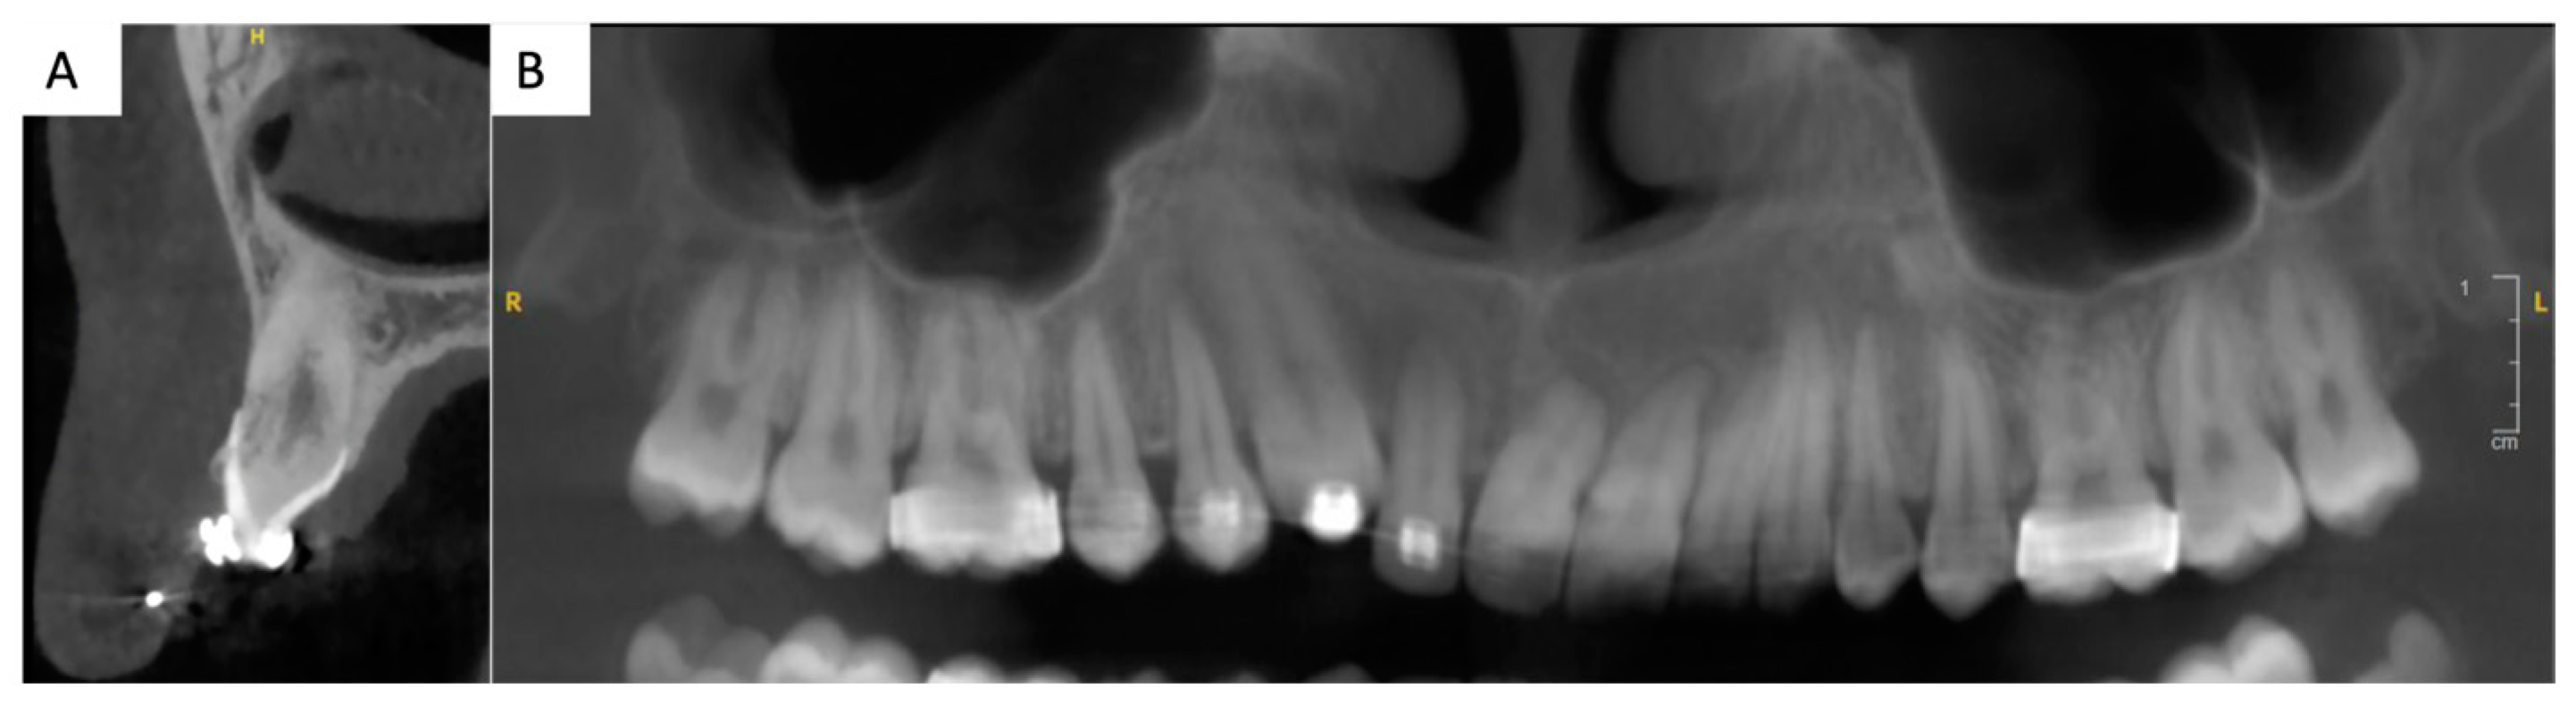

Figure 2. Three-dimensional imaging, CBCT (cone beam computed tomography): (A): sagittal section of tooth 13. Thin buccal and palatal cortical bone plates and proximity of the apex of 13 with the right nasal cavity can be noted. (B) Two-dimensional reconstruction of the upper jaw. Important root resorptions of the central maxillary incisors can be noted. A root resorption of the lateral incisor is also present.

Upon clinical and radiological examination (Figure 1, Figure 2 and Figure 3), the patient exhibited a harmonious face; a reduced lower facial height; an impacted, ankylosed, and severely infra-occluded right maxillary canine; an upper dental midline deviated 2 mm to the right; a skeletal class II associated with a class II division 1 malocclusion; and an iatrogenic clockwise cant of the maxillary occlusal plane with simultaneous adaptation of the mandibular arch. Several root resorptions were observed, with all maxillary incisors exhibiting signs of this phenomenon. However, the central incisors appeared to have undergone a particularly pronounced degree of root resorption. The clinical diagnosis of ankylosis of # 13 (upper left canine, World Dental Federation notation) was confirmed by the observation of a cant of the occlusal plane, a metallic sound after axial percussion, and a lack of mobility of the canine. A radiographic examination (Figure 2) revealed that the root was centred within the alveolar process. An external resorption with bone replacement was evident in the cervical region on the buccal side of the canine, indicative of tooth ankylosis. In contrast to the thicker palatal cortical bone, the buccal cortical plate was less than one millimetre thick.

A multidisciplinary consultation was convened between the departments of dentofacial orthopaedics, oral surgery, periodontics, and prosthodontics, with the objective of developing an optimal treatment that would honour the patient’s desire for an aesthetic restoration of the smile within a limited timeframe. In consideration of the functional and aesthetic requirements, as well as considering the residual vertical alveolar growth, it was determined that a fixed tooth-supported prosthetic rehabilitation of tooth # 13 was the optimal course of action, given the pre-existing multiple root resorptions [7] (Figure 2). This objective could be achieved through the correction of the occlusal plane cant and partial extraction of the upper right canine, in conjunction with a soft tissue surgery in the newly edentulous area.

The next step involved the decoronation of tooth # 13 while aiming to preserve the alveolar ridge. Due to the thin buccal cortical plate (<1 mm) (Figure 2), as well as the position and size of the canine, a full tooth extraction posed a risk of bone damage and could have resulted in an unpleasant gingival defect. To avoid such complications, after removal of the buccal flap, the crown of tooth # 13 was vertically divided into two parts using an orange contra-angle and fissure bur (H162SL.314.014 VPE 1 tungsten bur, Komet, Dublin, Ireland). Both fragments were then extracted, and the remaining root was progressively milled with a handpiece bone ball bur (H141.104.027 VPE 1 tungsten bur, Komet, Dublin, Ireland), while extensive irrigation and optical aids (Orascoptic loupes, Madison, WI, USA) were used to remove all residual enamel. Intra-operative radiographic controls were used to monitor the progress of the decoronation and assess the size of the residual root. An endodontic file (K file, size 15) was used to remove the remaining pulp parenchyma from the apical fragment, inducing intracanal bleeding and promoting supra-radicular blood clot formation (Figure 6). Sutures (5–0, Vicryl Rapide, Raritan, NJ, USA) were applied and the buccal margin was brought closer to the palatal margin to avoid scarring in the aesthetic zone.

Like any treatment plan, this one has its limitations. The presence of a small residual black triangle between teeth # 12 and # 13 is one of them. The reduced size of the papilla was anticipated in the beginning and was due to a reduced bone level. This drawback could have been limited with additional orthodontic treatment. However, invasive and risky treatment would have been necessary to improve this minor aesthetic inconvenience. For instance, in order to apically move the # 12 to # 13 contact point, thus improving the interdental papilla, stripping of the distal side of the # 12 tooth would have been necessary. This would have inevitably reduced the mesio-distal diameter of # 12 compared to # 22, leading to unpleasant smile aesthetics. Alternatively, further distal tilt of the # 12 root could have improved the situation of the inter-dental papilla as well. This treatment option has been excluded, as the # 13 and # 12 root were already fairly close to each other (Figure 2). For instance, further apical movement of the lateral incisor would have mandated its coronoplasty, as the incisal edge would have been placed lower than the aesthetic plane. Thus, the multidisciplinary team has decided against further orthodontic treatment because of the pre-existing root resorptions. Indeed, continuing orthodontic treatment could have worsened the existing root resorptions, therefore exposing the patient to the risk of premature tooth loss [7]. For the same reasons, orthodontic treatment has not considerably enhanced the bone architecture. In fact, orthodontic extrusion can facilitate bone remodelling and enhance the overall success of any prosthodontic rehabilitation. However, in this case, any further bone, gum, or occlusion optimisation could have been detrimental to the patient’s health and would have implied invasive treatment [7]. After an initial failure of the orthodontic treatment in another institution because of the ankylosed canine, the orthodontic treatment time was deemed exceedingly long and presented long-term risks. As a consequence, the treatment objectives were limited to the correction of the occlusal plane cant and prosthodontic rehabilitation of # 13, leaving the sagittal malocclusion untreated.